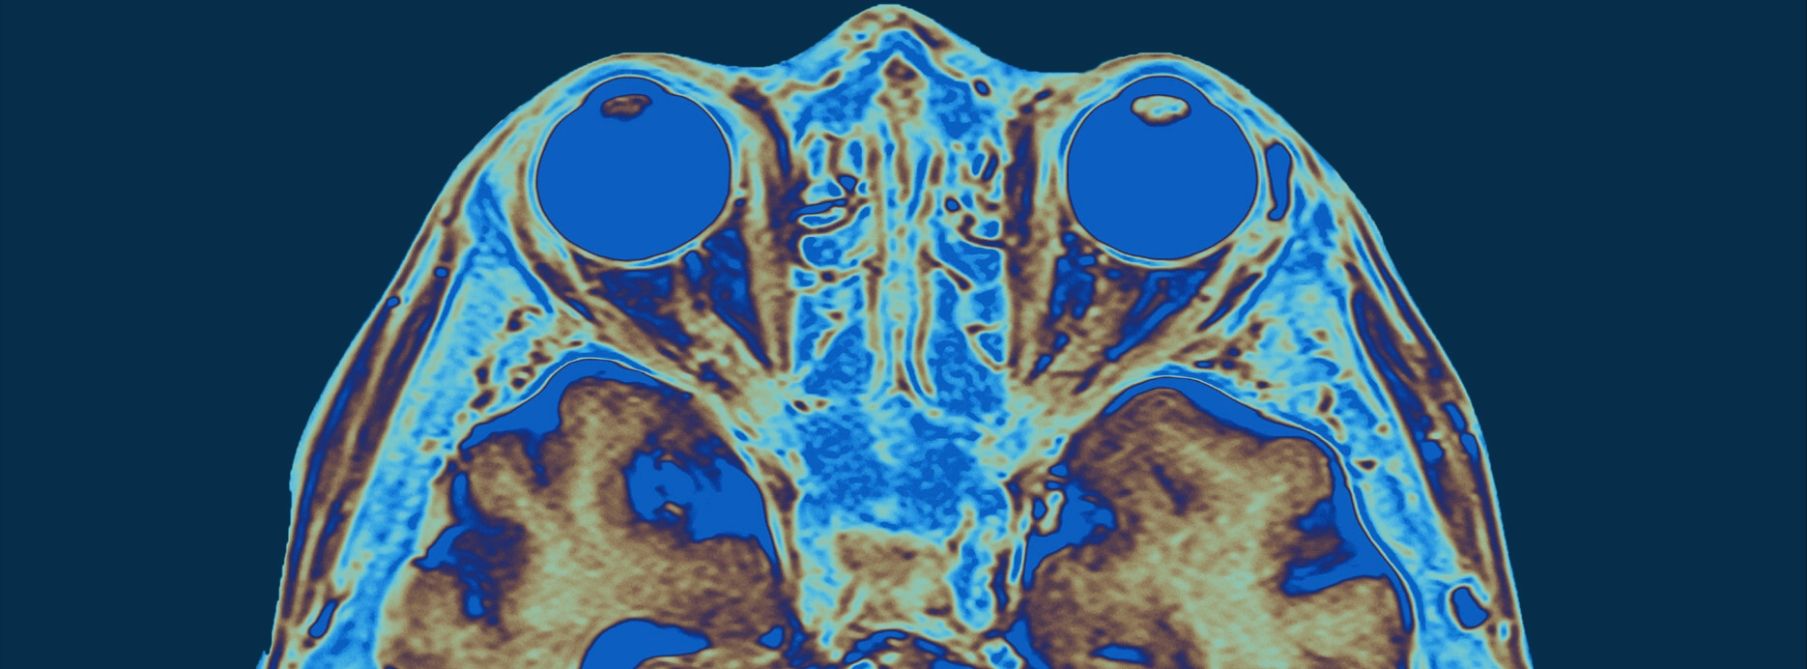

Deep Transcranial Magnetic Stimulation, also known as Deep TMS or dTMS, refers to a more effective and deeply penetrating form of TMS treatment, now possible using the newer generation of TMS technology.  The Brainsway® Corporation, developer of dTMS, has engineered the H1 dTMS coil that was approved by the FDA for the indication of treatment-resistant depression.  The H1 coil produces a magnetic pulse that stimulates a larger area than the traditional figure-8 coil used in regular TMS.  The stimulation also penetrates deeper, reaching 1.7 centimeters into the cortex.  The greater benefits of this therapy are connected to both the more complete stimulation of the target area, as well as some stimulation of the neighboring areas of the brain that interconnect with the target area. The risk of dramatically losing efficacy from deviating even just 1 mm from the target area is greatly diminished using a Brainsway® Deep TMS device, as compared to a traditional figure-8 coil, due to the larger and deeper area of stimulation.  This helps yield higher rates of both response and remission for treatment-resistant depression.

Deep TMS is performed using a Brainsway® dTMS machine equipped with an H1 coil instead of the “Figure-8” coil.  The magnetic pulse produced by the H1 coil is focused, but covers a broader area that a “Figure-8” coil.  The H1 pulse also reaches 1.7 cm below the surface of the skull.  A dTMS session using the H1 coil takes approximately 9-12 minutes in most cases, depending on the dose necessary.